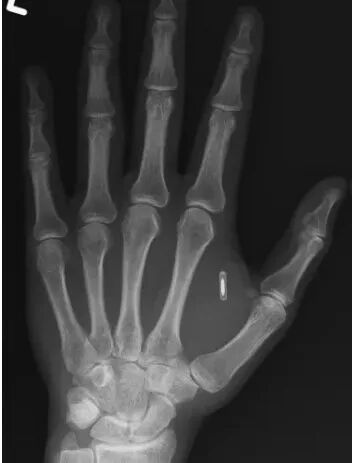

男子手部植入芯片忘记密码只能“暴力破解”

12 月 2 日消息,美国密苏里州一名魔术师突发奇想:将一枚电脑芯片植入自己的手掌,再用它表演一些有趣的魔术。可惜的是,他竟然忘了密码。

他在个人 Facebook 账号上分享了这段窘境,并附上了一张 X 光片,该 X 光片清晰显示那枚惹祸的微型芯片,就嵌在他的拇指与食指之间,轮廓分明。

他在 Facebook 帖子中解释道,多年前出于魔术表演的趣味性,他将一枚射频识别(RFID)微型芯片植入掌中。该芯片原本的设计是:当观众用带有 RFID 读取功能的智能手机触碰他的手时,即可触发他预设的魔术效果。

“但事实证明,反复让别人把手机按在我手上,试图找到他们手机 RFID 读取器的位置,根本谈不上神秘、神奇或令人惊叹,”他写道,“而且很多时候,观众的手机根本没开启这个功能。如果改用我自己的手机来扫描,又显然缺乏表演张力。”

故事的结局是:懂技术的朋友告诉他,唯一解锁芯片的办法,就是把 RFID 读取器绑在手掌上,“连续几天甚至几周”,通过“暴力破解”尝试所有可能的密码组合。于是,这枚芯片至今仍留在他手中,连同那个遗失的密码一起,成了无法访问的“体内遗迹”。